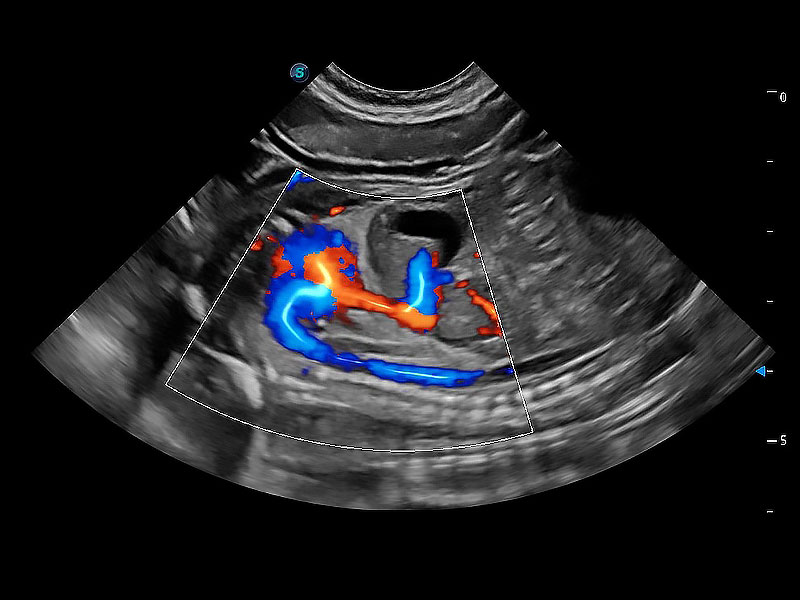

ProPet 80 配备了丰富的心脏探头群、先进的成像技术和专业的心脏测量工具,可帮助动物医生为不同体型和生理结构的动物提供心脏和心肌功能的全面评估。

实时用颜色表示心肌组织运动,观察和定量组织的运动情況,对快速检测与评估心肌的灌注和活性、电传导及心肌收缩和舒张功能等均能提供重要的诊断信息。

通过360度任意调节3条M型取样线,在同一心动周期上观察心脏不同位置的运动曲线,得到准确的心功能测量数据,有效评估心肌运动及左心室功能。